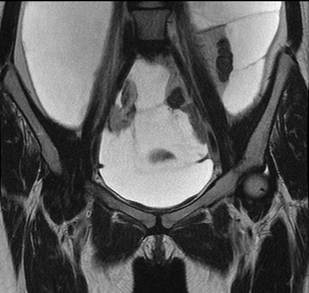

Se realizó una resonancia magnética de abdomen y pelvis que demostró la ocupación de todos los recesos peritoneales con líquido complejo de diferentes captaciones y septos multiloculados, la ocupación del espacio subfrénico derecho debido al desplazamiento tanto del hígado en sentido superior, como de las asas intestinales incluyendo el colon derecho en sentido central y en sentido posterior rechazando el colon descendente. No había compromiso retroperitoneal. Se encontró además una lesión quística dominante adyacente al pedículo ovárico derecho sin conformarse propiamente una masa ovárica, lo que hizo sospechar el origen en la trompa. Debido a la presentación clínica y a los resultados de la resonancia, se sospechó un pseudomixoma peritoneal de probable origen apendicular (Figuras 1,2,3).